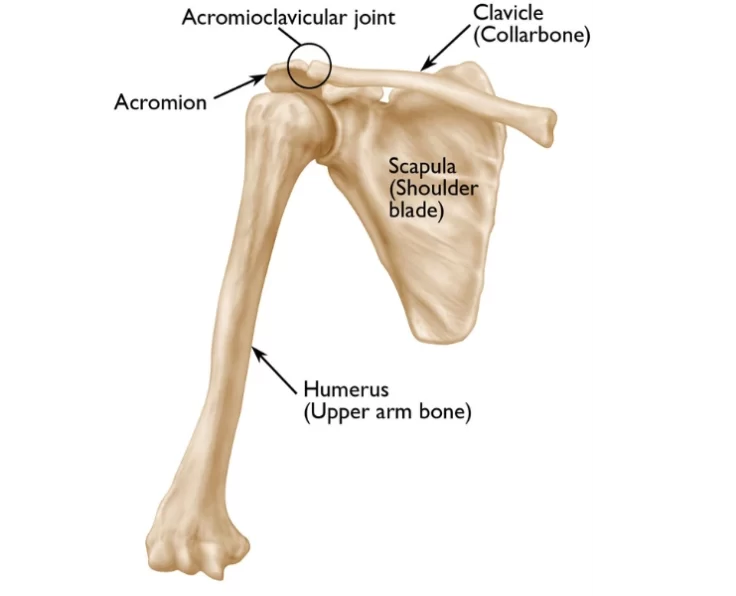

The upper arm bone, shoulder blade, and collarbone make up your shoulder joint, which is a ball and socket joint.

The shoulder joint is a ball-and-socket joint that joins the upper arm's (humerus) bone with the shoulder blade (scapula).

The acromioclavicular joint, often known as the AC joint, is positioned on the top of the shoulder, where the clavicle (collarbone) meets the acromion (shoulder…

The humerus (arm bone, which is the ball) and the glenoid (socket) are the two main components of your shoulder (socket).

Fractures and dislocations of the arms and shoulders are known as upper limb fractures and dislocations.

The shoulder is the most mobile joint in the body, it requires a complex system of structures to keep it stable during movement.